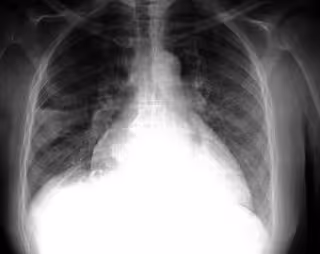

FLICKR/PULMONARY PATHOLOGY/CC BY-SA 2.0 - Archivo

La fibrosis pulmonar puede desarrollarse después de lesiones pulmonares, como infecciones, radiación o quimioterapia, o puede tener una causa desconocida, como en la fibrosis pulmonar idiopática (FPI). La FPI es un trastorno pulmonar progresivo y finalmente fatal que afecta a más de 150.000 pacientes al año en Estados Unidos y más de 5 millones en todo el mundo.